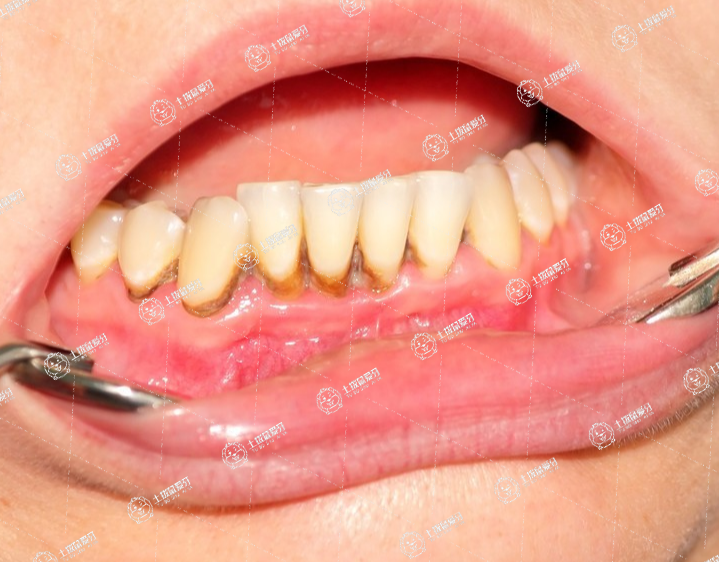

牙結(jié)石是長時間沉積在牙齒表面上鈣化的菌斑及軟垢,且菌斑形成薄膜覆蓋在結(jié)石上導(dǎo)致其不易被牙刷刷掉。牙結(jié)石常存留與牙根與牙齦的交界處,如果長時間不清理,容易滋生細(xì)菌,刺激牙齦,引發(fā)炎癥反應(yīng)導(dǎo)致口臭、牙齦紅腫、出血等。

所以需要患者規(guī)律清除牙結(jié)石,維護(hù)良好干凈的口腔環(huán)境。由于牙結(jié)石堅(jiān)硬且鄰近牙齦,在清理過程中,不可避免地會損傷牙齦表面黏膜而出血,所以清潔過后需要敷藥,促進(jìn)黏膜恢復(fù)。

洗牙結(jié)石對牙齒一般沒有危害,出現(xiàn)牙結(jié)石多數(shù)是由于口腔內(nèi)清潔不到位所導(dǎo)致的。如果牙結(jié)石長時間不清除,還可能引發(fā)多種口腔疾病,有可能會引起牙齦出血和牙齦腫痛等現(xiàn)象。還可能會引起牙齦萎縮和牙齒鈣化的癥狀,有的還會出現(xiàn)口臭等癥狀等。如果出現(xiàn)牙結(jié)石的癥狀,應(yīng)到醫(yī)院口腔科進(jìn)行專業(yè)的去除,日常要注意口腔衛(wèi)生,盡量要選擇合適的口腔清潔工具。